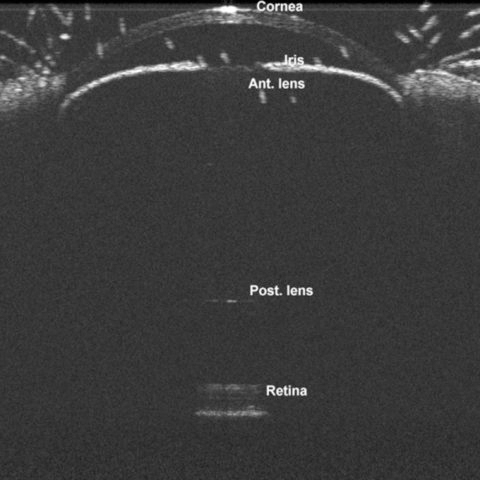

Figure 1 of Wu, Mol Vis 2015; 21:138-147.

Figure 1. Representative spectral-domain optical coherence tomography image of a mouse eye.